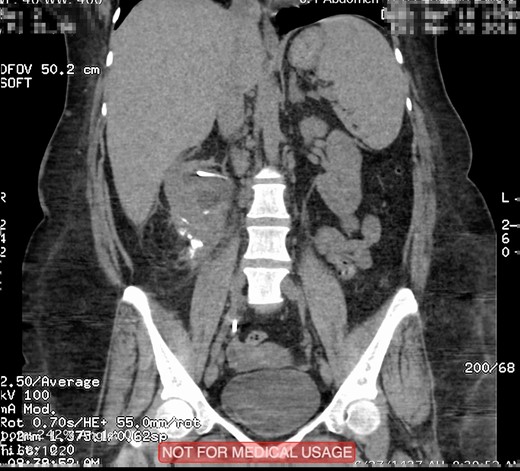

This is a 45-year-old female patient known to have diabetes mellitus and old cerebrovascular attack presented with right flank pain. Laboratory investigations revealed normal WBC count with a hemoglobin 10.4 mg/l. Radiological investigation showed right a 20 mm right renal stone (Fig. 1). Patient underwent FURS-L using a 10/12Fr Ureteral Access sheath. We did endoscopic renal exploration plus laser lithotripsy using Flex-Xc STORZ. The irrigation was under hydrostatic pressure of 80 cm H2O. The procedure was uneventful with an operative duration of 88 minutes. However, severe extravasation was noted at the end (Fig. 2). Six hours postoperatively the patient started to have high grade fever with a sudden drop of hemoglobin level to 6.6 mg/l. Immediate abdominopelvic CT scan with contrast was carried out showing severe right subcapsular renal hematoma. This complication was managed conservatively through proper antibiotics, blood transfusion and good hydration for 7 days. The patient was seen in the outpatient clinic 2 months later with a new abdominopelvic CT scan which showed a regression of subcapsular renal hematoma and surprisingly migration of stone fragments into the regressed subcapsular hematoma (Fig. 3). On the other hand, the upper urinary tract was free of stones.

Plain abdominopelvic CT scan, coronal view (A) and axial view (B) showing right renal pelvic stone measuring 20 mm.